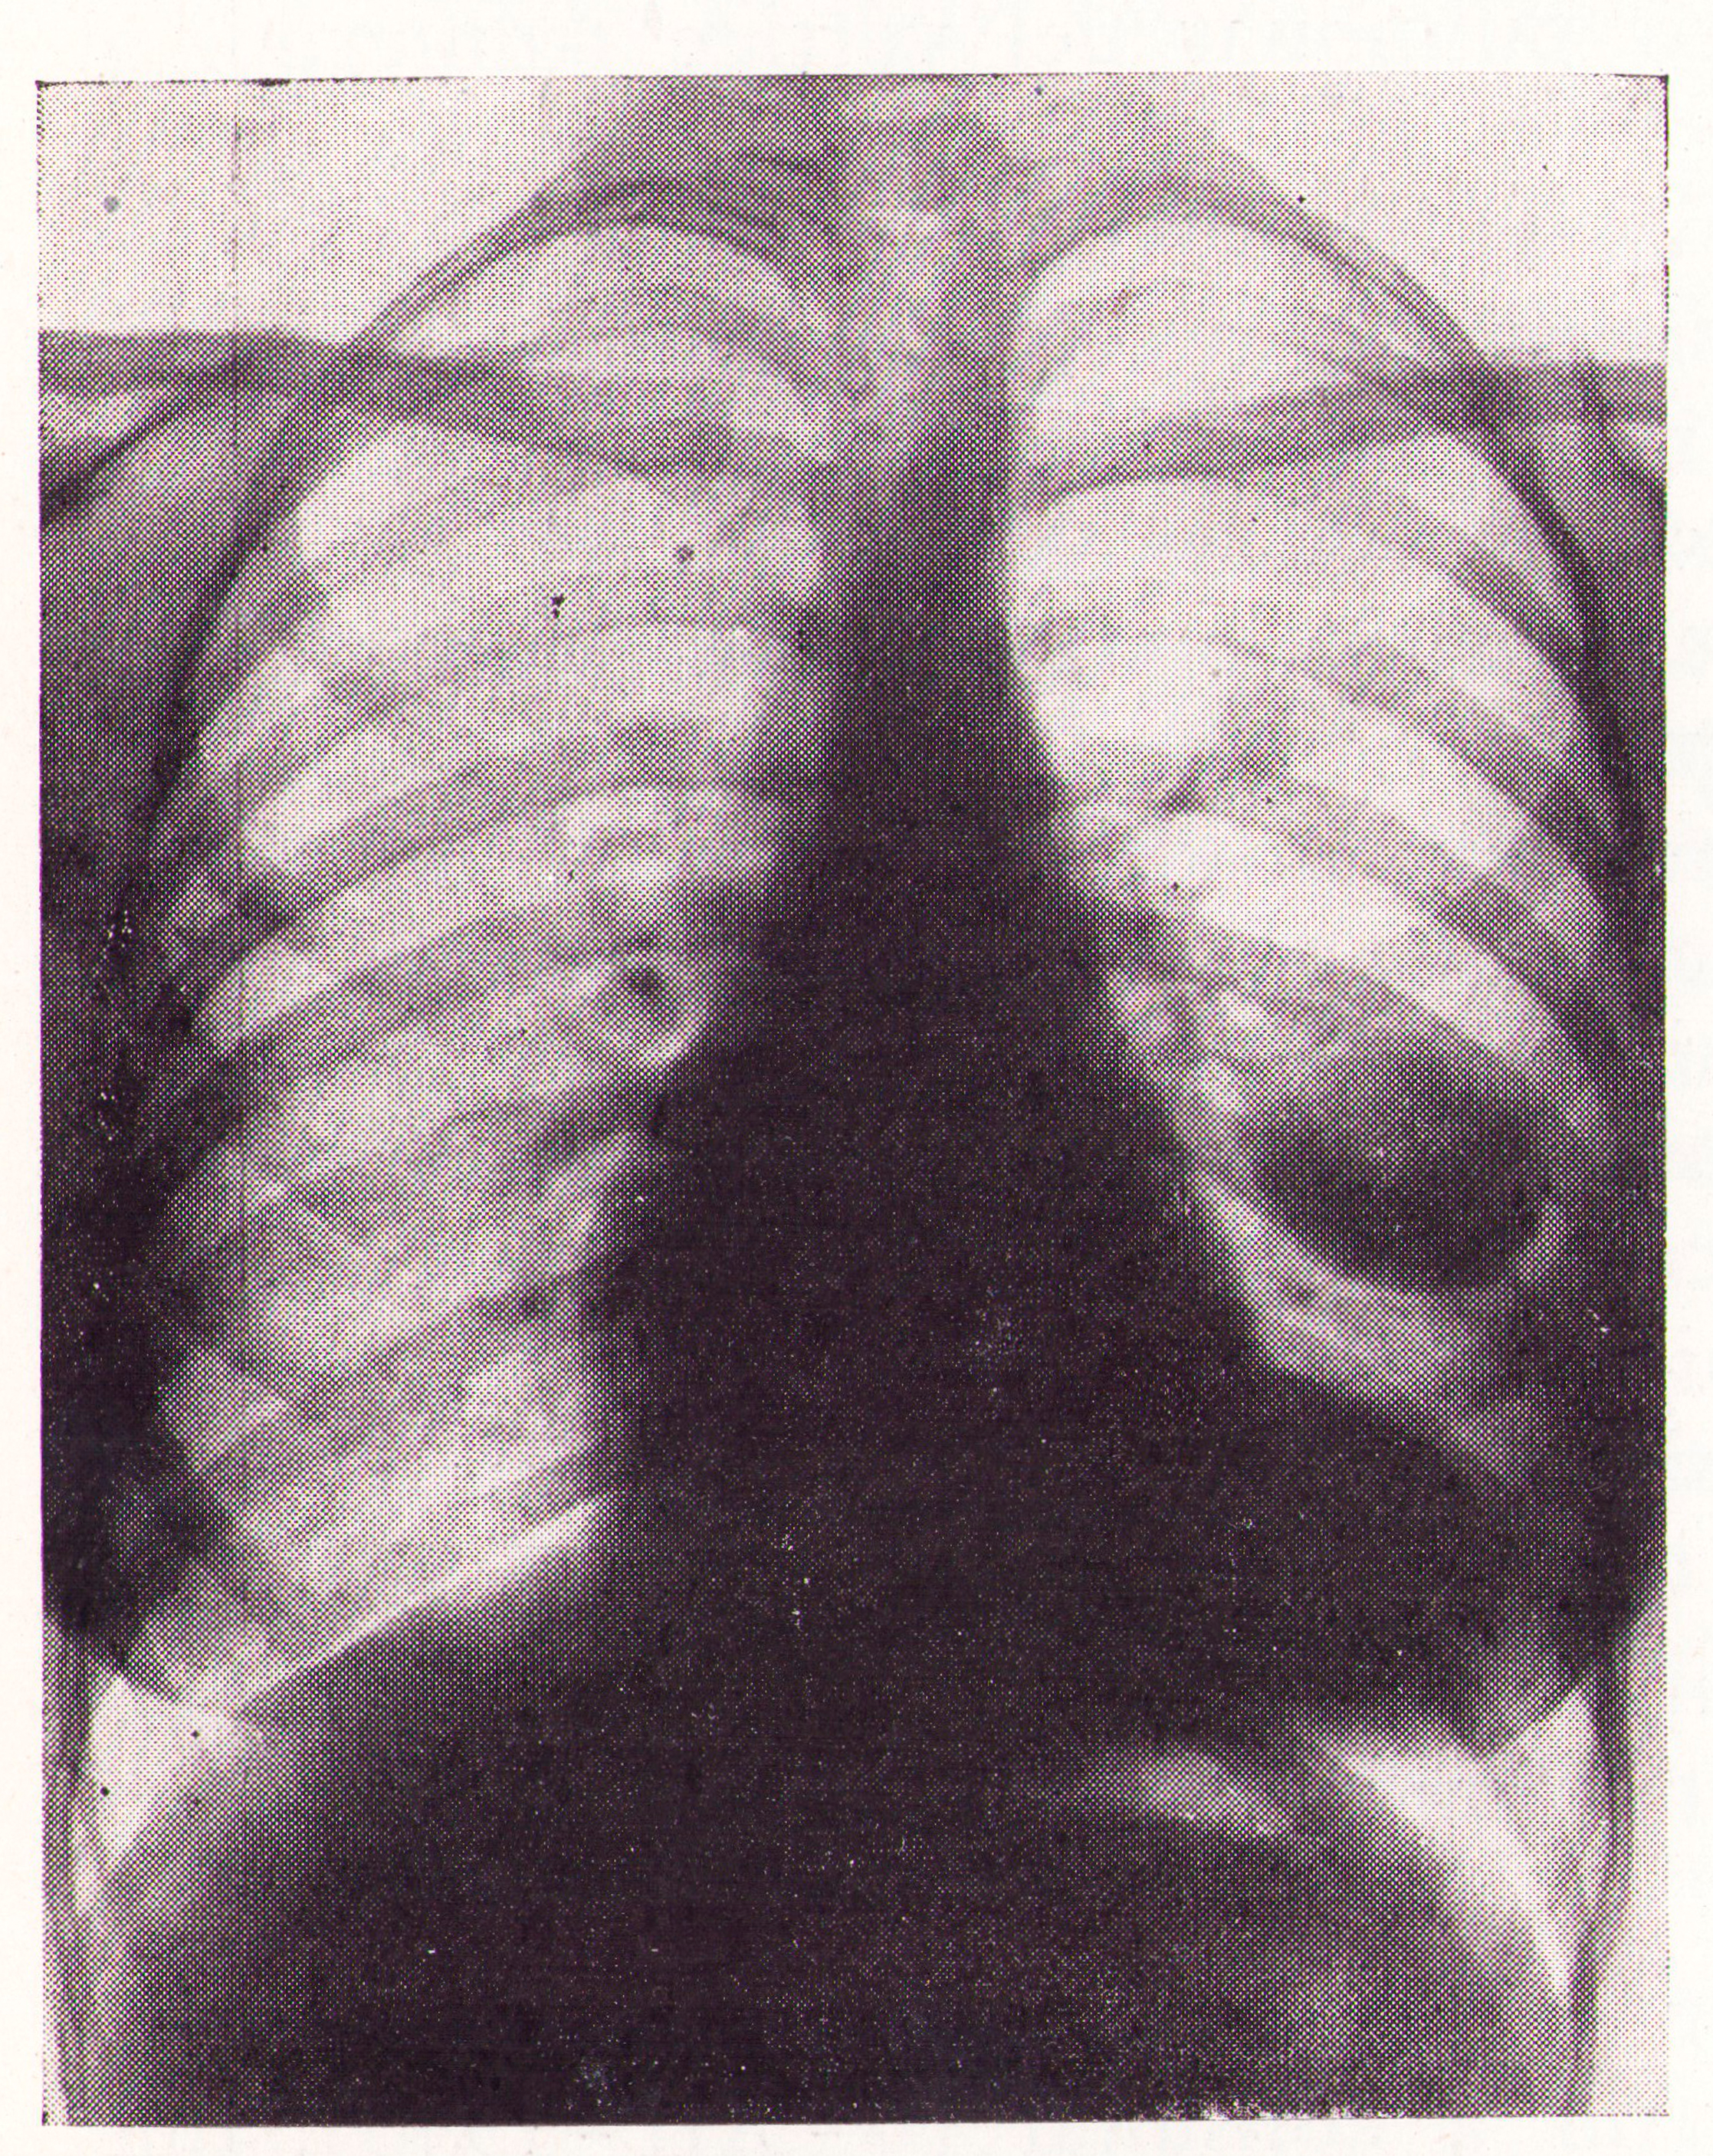

Quistes de pulmón izquierdo

Fig.1. Revista Española de ciencias médicas, Clínica y laboratorio, 1953.